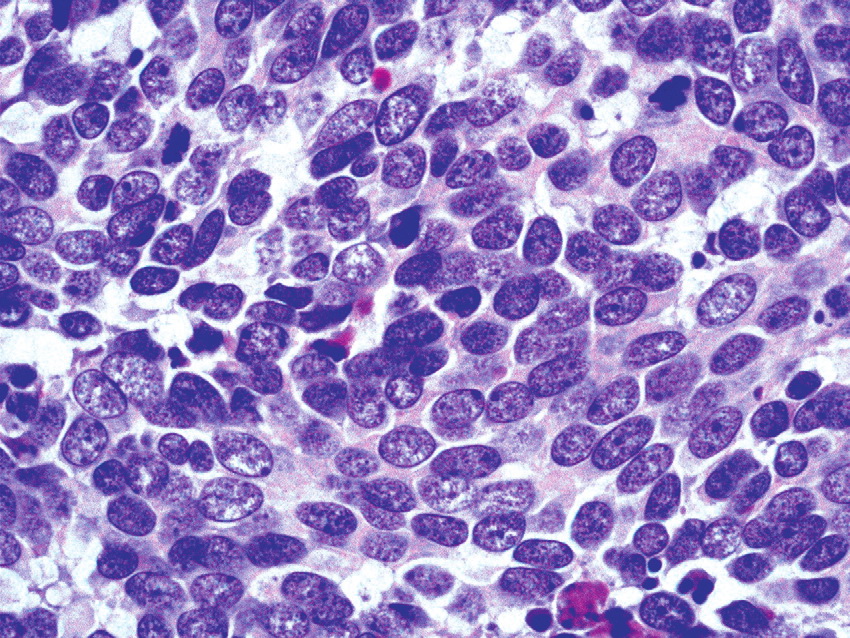

merkel-cell-carcinoma